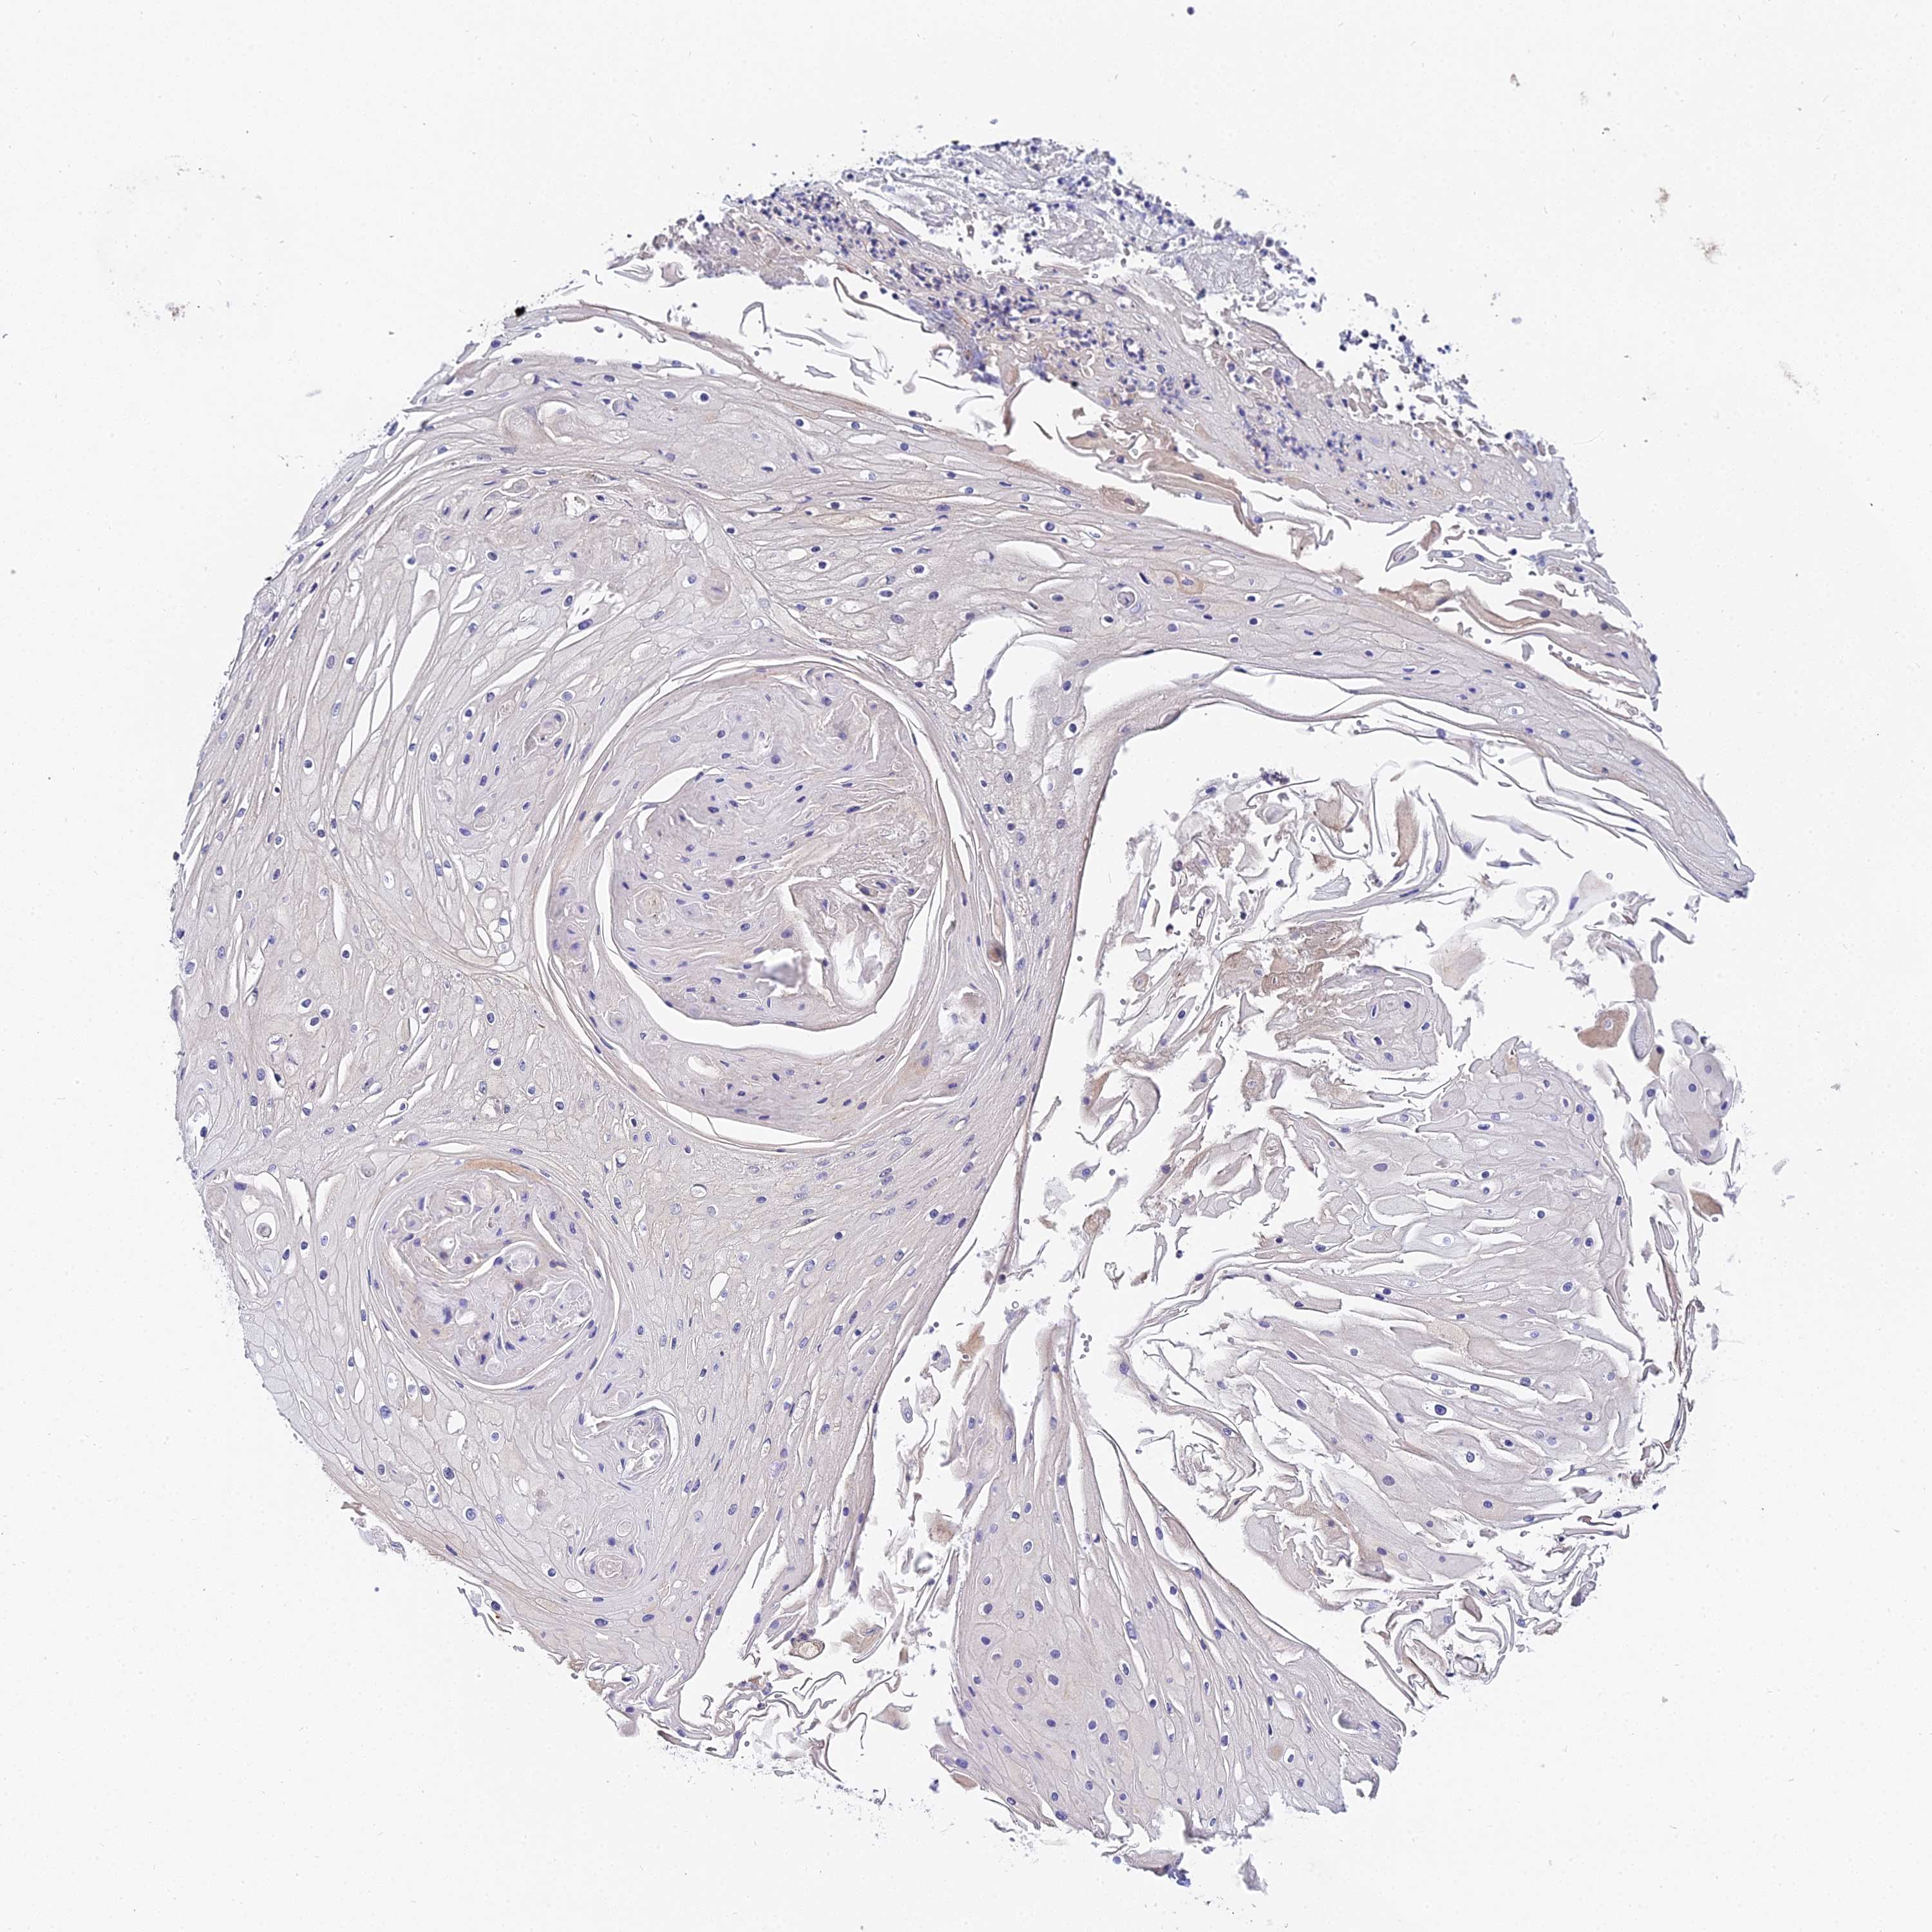

SKIN CANCER - Protein expressioni

A mouse-over function shows sample information and annotation data. Click on an image to view it in a full screen mode. Samples can be filtered based on level of antibody staining by selecting one or several of the following categories: high, medium, low and not detected. The assay and annotation is described here.

Each image is clickable and will lead to virtual microscopy that enables deeper exploration of all samples and also displays staining intensity scores, fraction scores and subcellular localization as well as patient and tissue information for each sample.

Antibody HPA020485

Staining

Not detected

Intensity

Negative

Quantity

None

Location

Squamous cell carcinoma, NOS